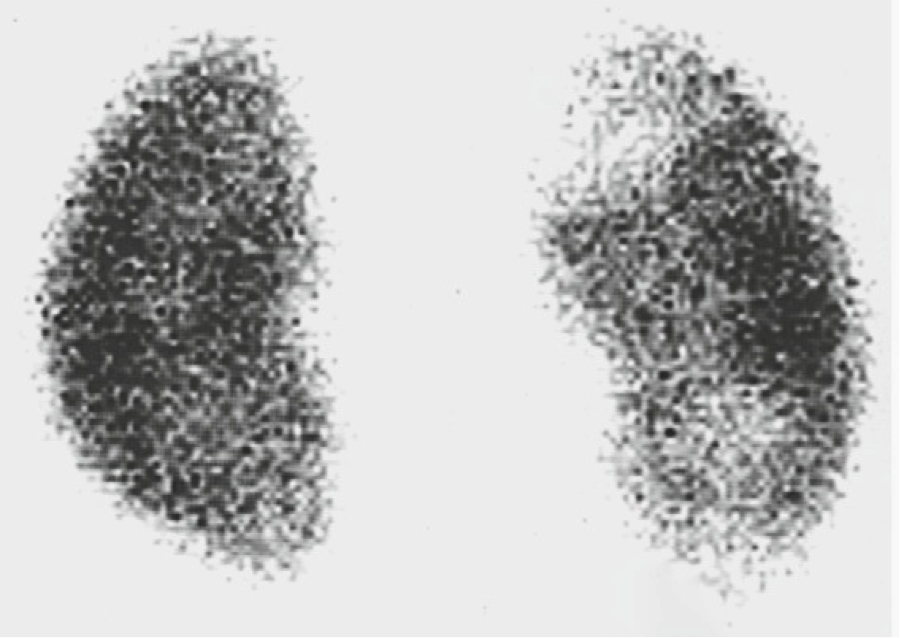

In pediatric patients in whom there is clinical difficulty in distinguishing an upper from a lower UTI, cortical scintigraphy using dimercaptosuccinic acid (DMSA) has been advocated as being the most sensitive test. In the case of pyelonephritis, this study demonstrates single or multiple areas of lack of renal uptake of the radiotracer. These areas tend to be triangular and peripheral.

Renal scarring (cortical thinning)

vs

Fetal lobulation

The loss of renal cortical substance as seen by ultrasound, most commonly at one of the renal poles, is suggestive of the diagnosis.

This should not be confused with fetal lobulation (also known as an interrenicular septum, a normal variant.

In pyelonephrotic scarring, the indentations of the renal contour

tend to overlie the renal calyces, whereas in fetal lobulation, the indentations are between renal calyces.